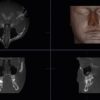

- Cấy ghép implant: đánh giá mật độ và thể tích xương hàm, vị trí ống thần kinh

- Phẫu thuật miệng hàm mặt: lên kế hoạch cắt xương, u nang, u xương hàm

- Đánh giá TMJ: hình ảnh lồi cầu 3D, không gian khớp